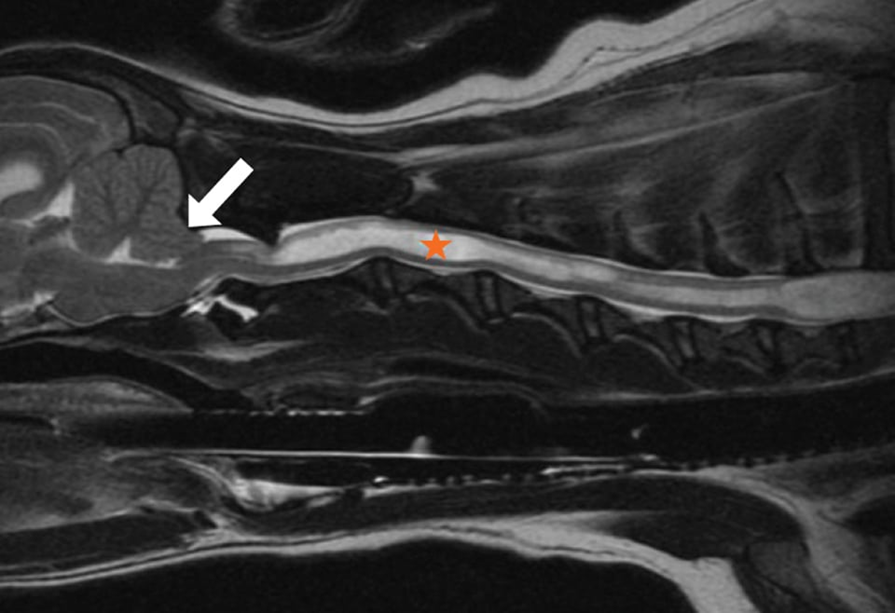

What pathology is shown in this image?

Myelomalacia of the spinal cord following IVDD, probably a small dog, poor prognosis